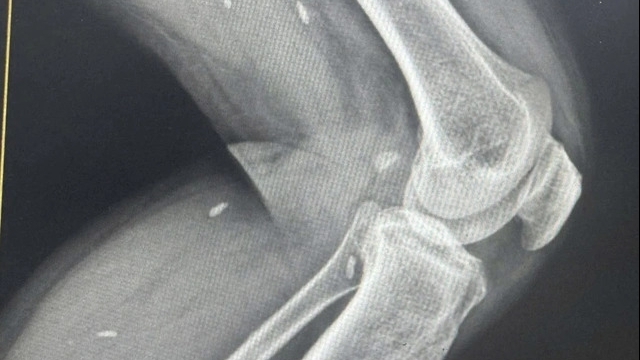

| Nam thanh niên bị máy cưa cắt xuyên thấu bụng mất máu, lộ quai ruột được kích hoạt báo động đỏ cứu sống. |